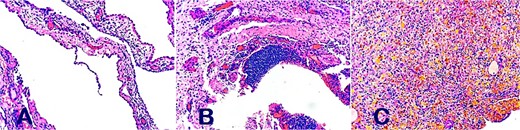

A follow-up echocardiogram 15 days after discharge showed a moderate recurrence of pericardial effusion, with hyperechoic nodular images at the posterior level, without causing hemodynamic repercussions, so a pleuropericardial window was made by lateral thoracotomy with drainage and sample analysis, where a thickened pericardium was evident, with the presence of nodular masses of 2 cm in diameter, between 6 and 8 units, with abundant bloody tissue adhered to the inner surface of the posterior pericardium which was resected, and 100 ml of serohematic pericardial fluid was drained. The histopathological analysis of pericardial tissue showed characteristics of papillary endothelial hyperplasia compatible with pericardial lymphangioma (Fig. 2).

Histopathological analysis of papillary endothelial hyperplasia compatible with pericardial lymphangioma on (A, B, and C).